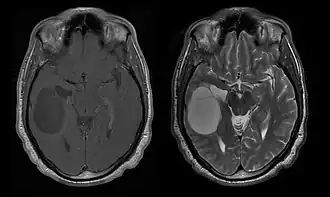

Primaire CZS-lymfomen

Primair lymfoom van het centrale zenuwstelsel is goed voor ongeveer 2 procent naar 3 procent van alle hersentumoren bij patiënten met een normaal immuunsysteem. Ze komen vaker voor bij mannen boven de 55 tot 60 jaar op. Bijna de helft van alle lymfomen komt voor bij patiënten ouder dan 60 jaar en ongeveer een kwart bij patiënten ouder dan 70 jaar jaar op. De incidentie lijkt toe te nemen met de leeftijd, maar de reden is nog steeds onduidelijk. Patiënten met een verzwakt immuunsysteem lopen een groter risico op het ontwikkelen van CZS-lymfoom, dus degenen die een orgaantransplantatie hebben ondergaan, hebben een aangeboren immunodeficiëntie of auto-immuunziekte, of zijn geïnfecteerd met het humaan immunodeficiëntievirus. HIV-geassocieerde hersenlymfomen zijn geassocieerd met het Epstein-Barr-virus, vooral bij patiënten met CD4-lymfocytentellingen van minder dan 500 cellen per kubieke millimeter in het bloed. De meeste CZS-lymfomen zijn grote B-cellymfomen van het type.

Patiënten lijden aan een verscheidenheid aan karakteristieke symptomen van een focale of multifocale massieve laesie. MRI toont meestal tumoren met homogene contrastversterking in de diepe periventriculaire witte stof. Multifocaliteit en inhomogene versterking zijn typisch voor patiënten met een verzwakt immuunsysteem. Analyse van CZS-lymfoom is uiterst belangrijk bij de differentiële diagnose van hersenneoplasie. Opgemerkt moet worden dat de toediening van corticosteroïden kan leiden tot het volledig verdwijnen van de versterking, waardoor de diagnose van de laesies moeilijk wordt. Als daarom CZS-lymfoom moet worden overwogen bij de differentiële diagnose, moeten corticosteroïden worden vermeden, tenzij het massa-effect een ernstig en onmiddellijk probleem bij de patiënt veroorzaakt.

Biopsie van de vermoedelijke laesie is cruciaal. In tegenstelling tot systemisch grootcellig B-cellymfoom, waarbij zowel chemotherapie als radiotherapie effectief zijn en de behandeling van gelokaliseerde laesies curatief is, reageert lymfoom van het centrale zenuwstelsel doorgaans op initiële therapie, maar keert daarna terug. Net als bij systemisch lymfoom is de rol van chirurgie voornamelijk beperkt tot het verkrijgen van geschikte weefselmonsters voor diagnose.